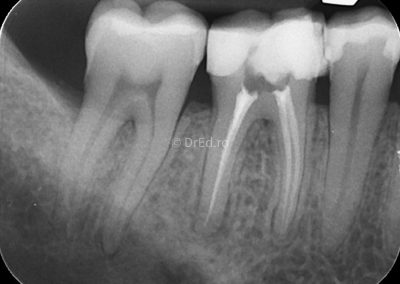

Galerie

Toate imaginile, fotografiile și radiografiile publicate pe acest site sunt protejate prin drepturi de autor și constituie proprietatea exclusivă a Dred.ro.

Aceste materiale sunt furnizate exclusiv în scop informativ și educațional și nu conțin date cu caracter personal sau informații care permit identificarea pacienților, în concordanță cu legislația privind protecția datelor cu caracter personal și GDPR.

Reproducerea, copierea, distribuirea, publicarea, transmiterea, modificarea sau orice altă utilizare, integrală ori parțială, a acestor materiale, în orice formă și prin orice mijloace, fără consimțământul prealabil scris al titularului drepturilor, este strict interzisă și poate atrage răspunderea civilă și/sau penală, în condițiile legii aplicabile privind drepturile de autor și protecția proprietății intelectuale.